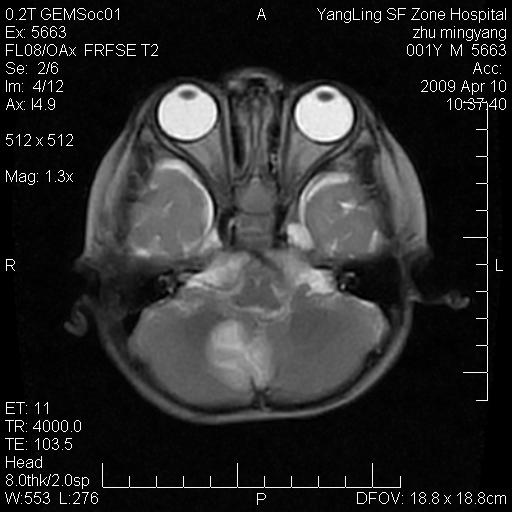

患者:1岁半,两天前外伤收住我院,ct检查小脑占位

考虑星形细胞瘤,建议增强

髓母细胞瘤或血管母细胞瘤,增强后可以鉴别;影像资料见 <。鱼博浪老师的《中枢神经系统ct与mr鉴别诊断》 小脑部肿瘤章节。

髓母细胞瘤或血管母细胞瘤!支持!

支持考虑髓母细胞瘤

考虑----髓母细胞瘤可能性大

考虑髓母细胞瘤或室管膜瘤。

支持髓母细胞瘤。

考虑髓母细胞瘤。

考虑髓母细胞瘤或星形细胞瘤

考虑髓母细胞瘤.

小脑肿瘤.考虑髓母细胞瘤可能.

就病灶部位及临床资料首先考虑髓母.